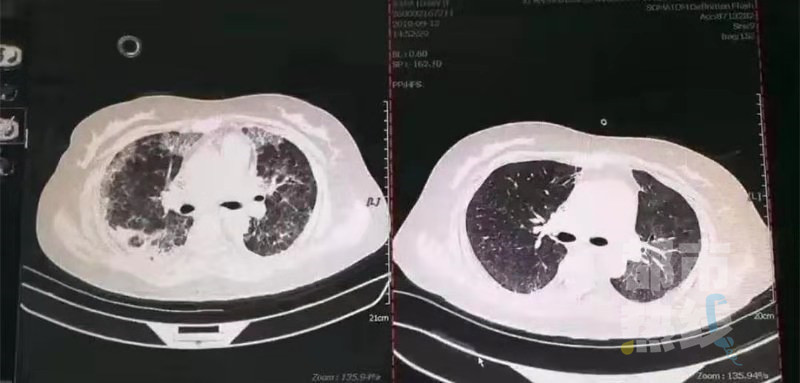

在诊断的过程中,一个最具有诊断意义的病菌浮出水面,那就是罕见的耶氏肺孢子菌,也就是大家经常能听到的“卡肺”。“卡肺”一般多见于艾滋病患者,但近年来,像荣女士这样的非艾滋病患者出现“卡肺”的偶有发生。这个疾病起病急,如果不及时诊断和处理,死亡率很高。